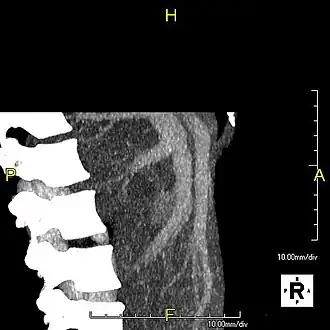

Lateral MIP view in the same patient as previous image -

With the recent advances of noninvasive imaging, living liver donors usually have to undergo imaging examinations for liver anatomy to decide if the anatomy is feasible for donation. The evaluation is usually performed by multidetector row computed tomography (MDCT) and magnetic resonance imaging (MRI). MDCT is good in vascular anatomy and volumetry. MRI is used for biliary tree anatomy. Donors with very unusual vascular anatomy, which makes them unsuitable for donation, could be screened out to avoid unnecessary operations.

-

MDCT image. Arterial anatomy contraindicated for liver donation -

MDCT image. Portal venous anatomy contraindicated for liver donation -

MDCT image. 3D image created by MDCT can clearly visualize the liver, measure the liver volume, and plan the dissection plane to facilitate the liver transplantation procedure. -

Phase contrast CT image. Contrast is perfusing the right liver but not the left due to a left portal vein thrombus.